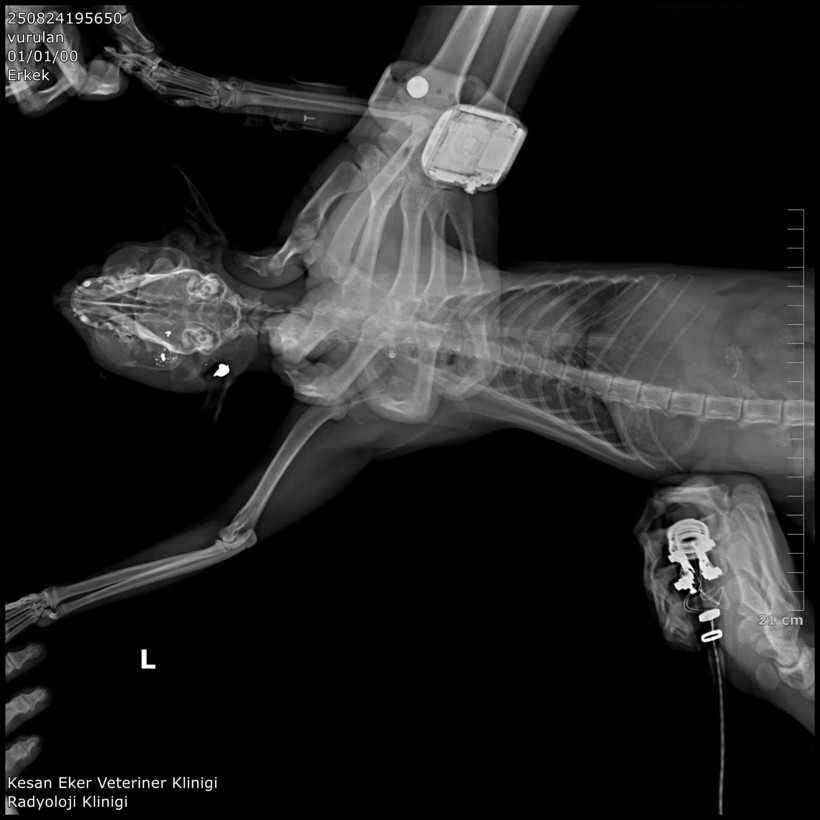

Klinik raporunda, 'ateşli silah yaralanması ile uyumlu patolojiler' tespit edilmesi, hayvanların tüfek mermisi ile öldüğüne dair bulguların bulunduğu ifade edildi. Bülbül, güvenlik kamera görüntülerinden komşusu K.G.'den şüphelenmeye başladı. Görüntülerde K.G.'nin bahçesine giren bazı kedilerin birden kaçtığı gözlemlendi.

Hüseyin Bülbül'ün avukatı, Edirne Barosu Keşan Temsilcisi ve Hayvan Hakları Komisyonu Başkanı Büşra Ağır Ürkmez, kedilerin 2018 yılından bu yana sistematik olarak öldürüldüğünü vurgulayarak, “En somut adımlar, 24 Ağustos 2025 tarihinden itibaren Hüseyin Bülbül'ün şikayet etmesi ile başlamıştır. İlk celsede deliller toplandı ve balistik rapor dosyaya sunuldu. Şüpheli, suçu işlemediğini beyan etse de mevcut deliller ve tanık ifadeleri, gerçekleri yansıtmadığını göstermektedir. Bu davanın takipçisi olacağız” şeklinde konuştu.

K.G.'nin kedileri bahçesinde av tüfeği ile vurduğunu belirten Ürkmez, “Buna dair delilleri dosyamıza sunduk. Ayrıca, veteriner ön raporunda da kedilerin ölümünde mermi parçalarına rastlandığı açıkça belirtilmiştir. Kamera kayıtlarını da delil olarak sunmuş bulunmaktayız. '5199 sayılı Hayvan Haklarını Koruma Kanunu' kapsamında şüphelinin ceza alması için her türlü çabayı göstereceğiz. Nihai kararı mahkeme verecektir. Şüphelinin yurtdışına çıkışı ve adli kontrolü devam etmektedir” ifadelerini kullandı.